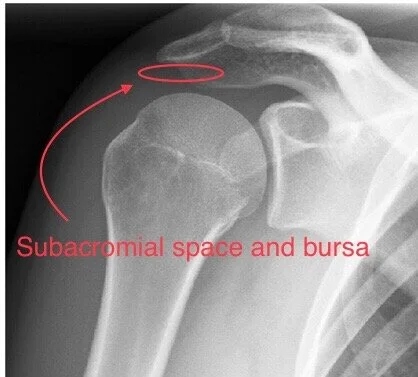

Four muscles with their corresponding tendons (known as the rotator cuff) work as a team and move the shoulder in a coordinated manor. The tendons pass in a space under the roof of the shoulder joint (acromion) known as the subacromial space. Overlying the tendons there is a fluid filled area of tissue - subacromial bursa. The subacromial bursa helps the rotator cuff tendons move smoothly beneath the acromion.

Conditions which effect coordinated rotator cuff function can result in abnormal shoulder movement which in turn causes irritation and inflammation to the subacromial bursa.